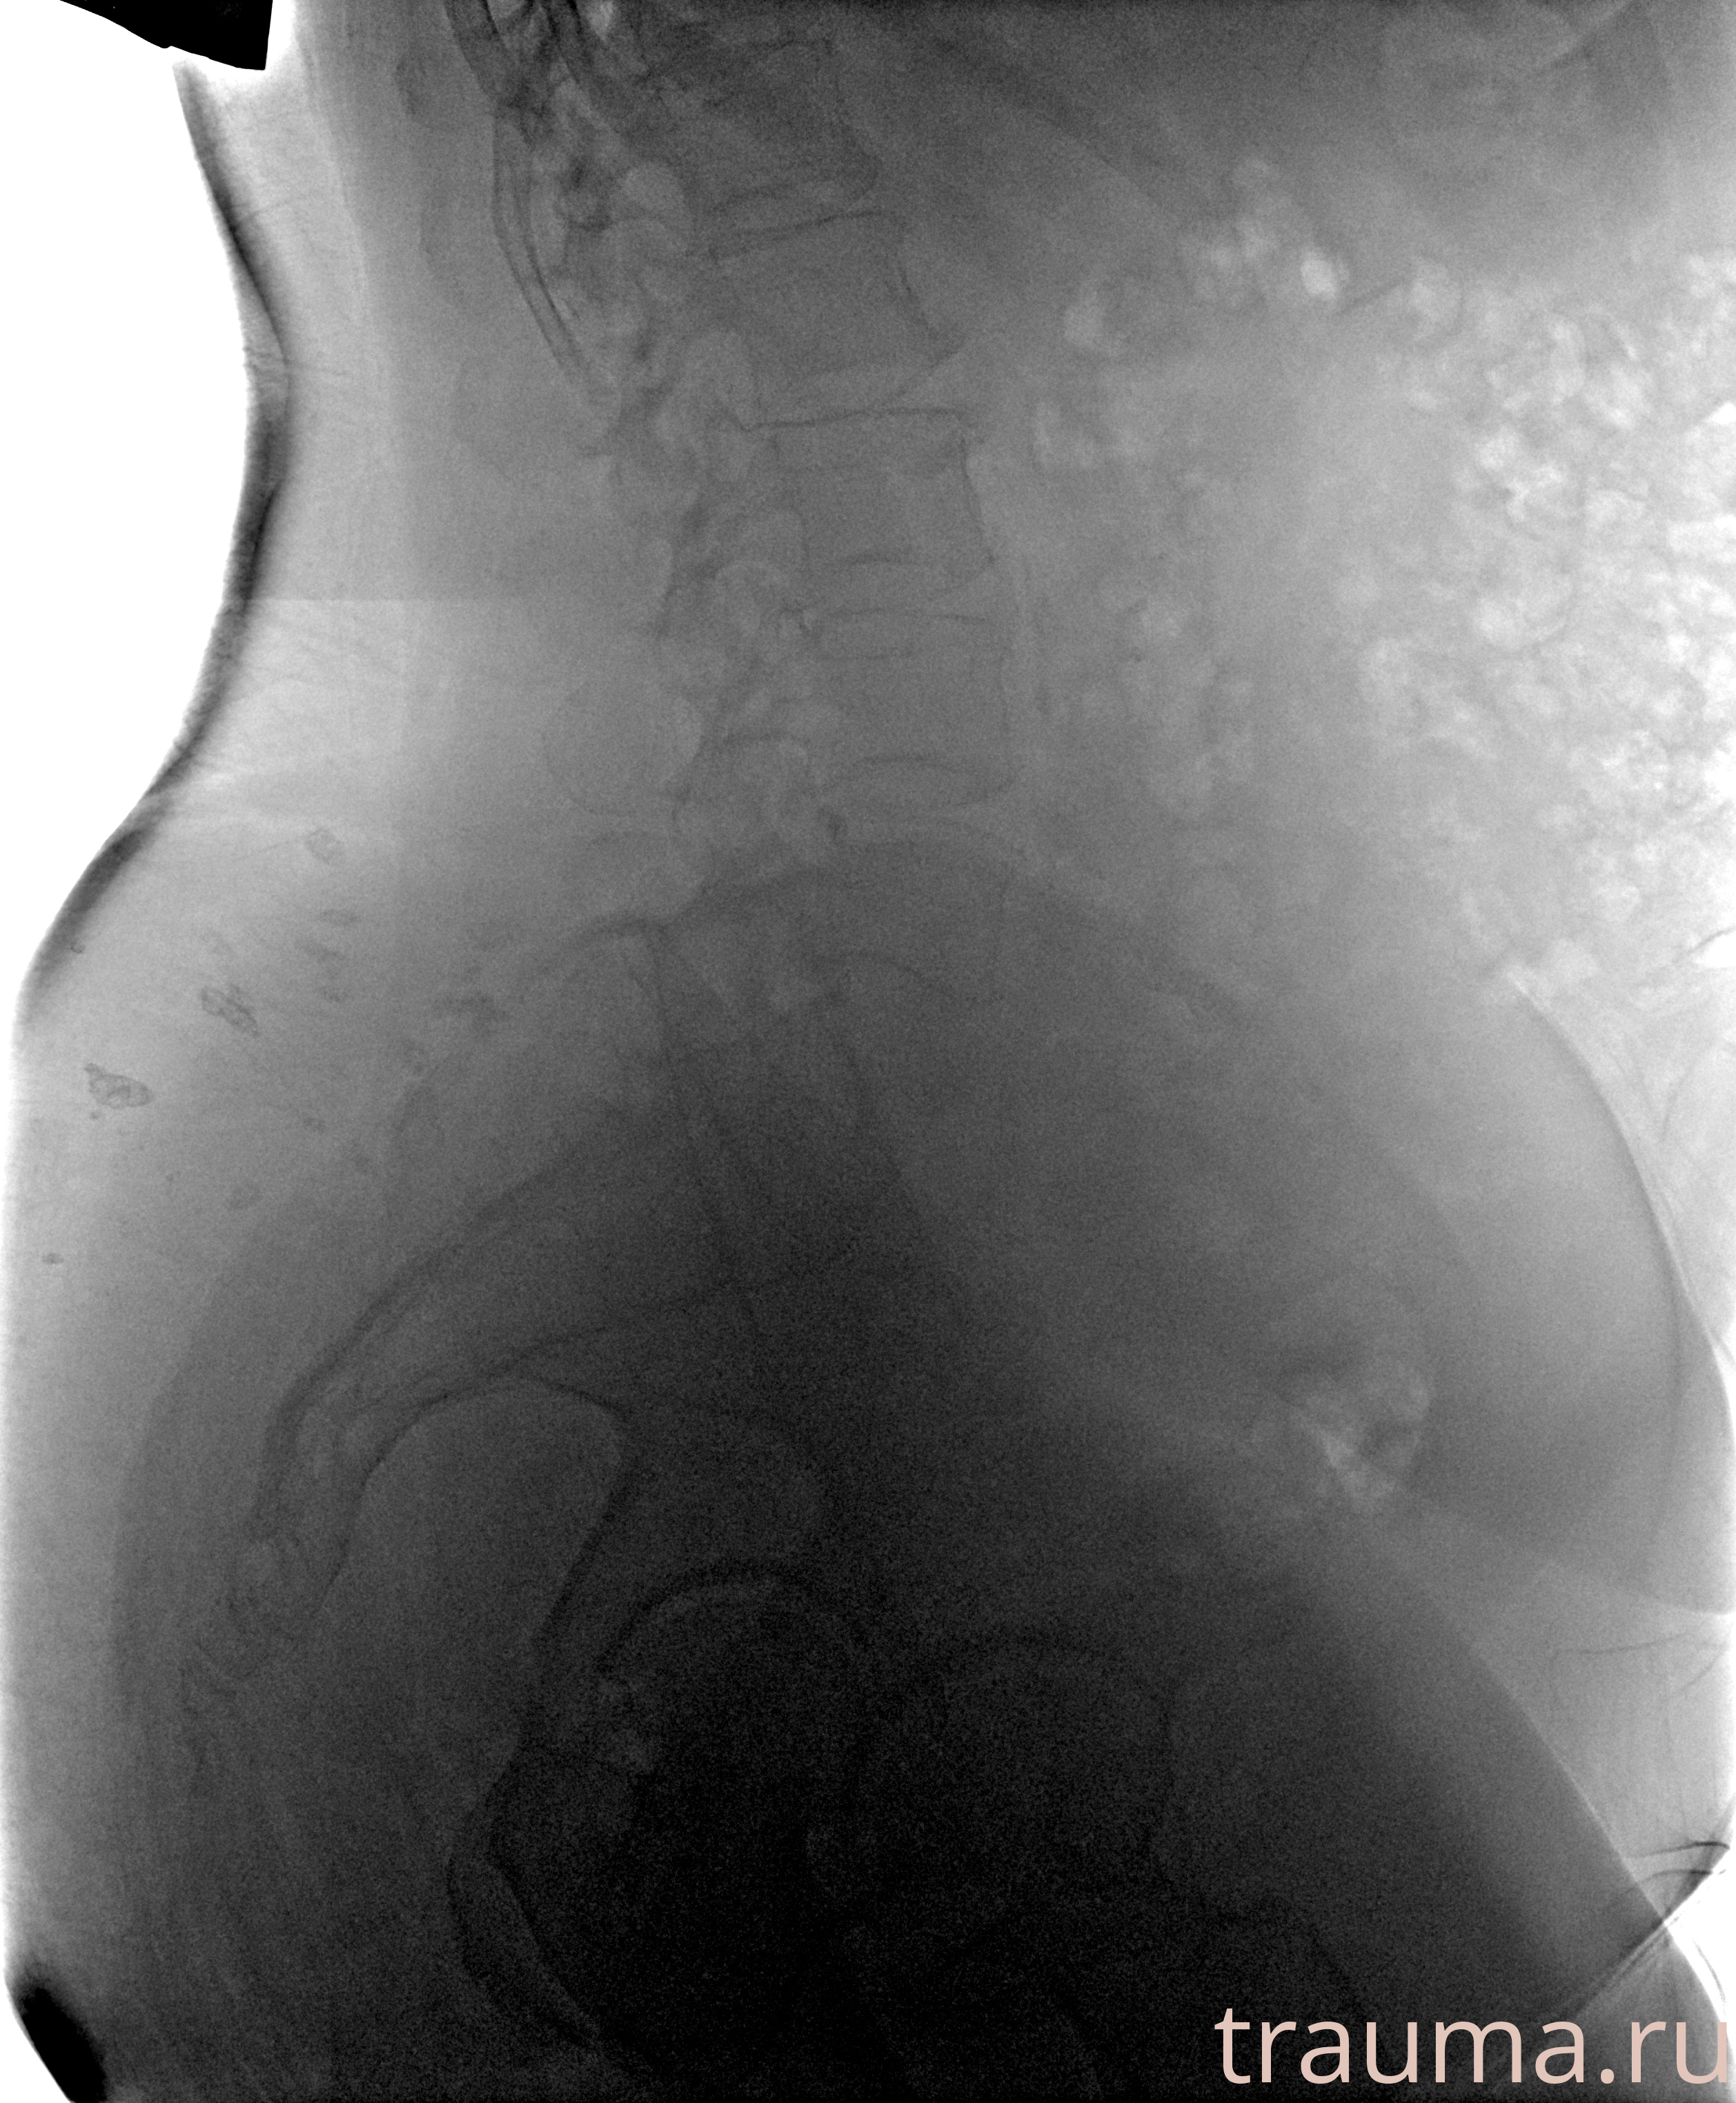

Рентген на дому: по вашему адресу приезжает врач-рентгенолог, травматолог-ортопед с мобильным рентгеновским аппаратом, проводит диагностику травмы или заболевания, делает необходимые рентгенограммы, дает рекомендации по дальнейшему лечению. Получить качественные снимки в домашних условиях возможно благодаря уникальной методике, разработанной МосРентген Центром для института  Склифосовского